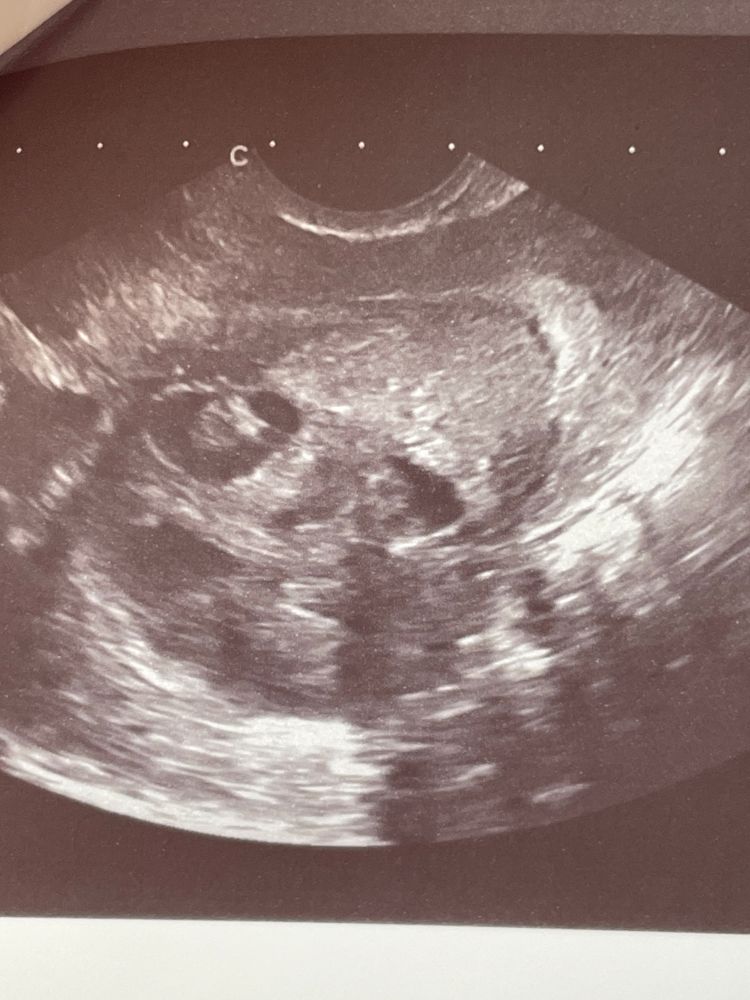

1 фото. В апреле обнаружили образование в левом углу матки, 10 мм - мнение врача «обычная киста» (1 апреля)